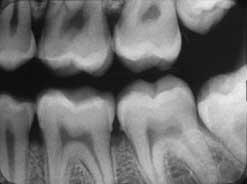

Es importante alinear el patrón de salida del haz con la película para evitar el «corte de cono». Estas dos imágenes muestran cortes de cono causados por la desalineación de conos redondos y rectangulares, respectivamente.